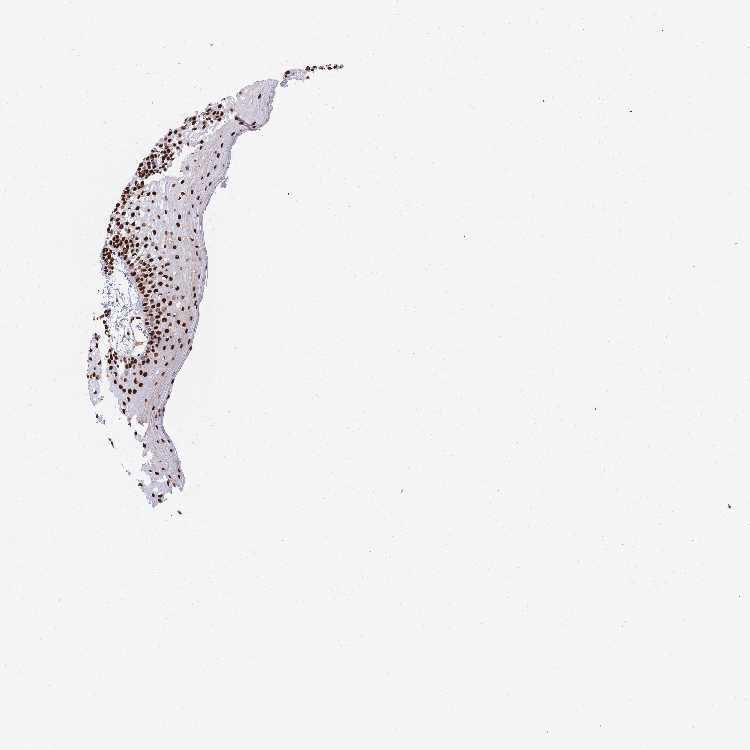

TISSUE PRIMARY DATA ORAL MUCOSA Show tissue menu

ORAL MUCOSA - Antibody stainingi

Antibody staining in the annotated cell types in the current human tissue is reported as not detected, low, medium, or high, based on conventional immunohistochemistry profiling in selected tissues. This score is based on the combination of the staining intensity and fraction of stained cells.

Each image is clickable and will lead to virtual microscopy that enables deeper exploration of all samples and also displays staining intensity scores, fraction scores and subcellular localization as well as patient and tissue information for each sample.

Antibody HPA046290Antibody HPA049475Antibody CAB046477

Squamous epithelial cells HighMediumHigh